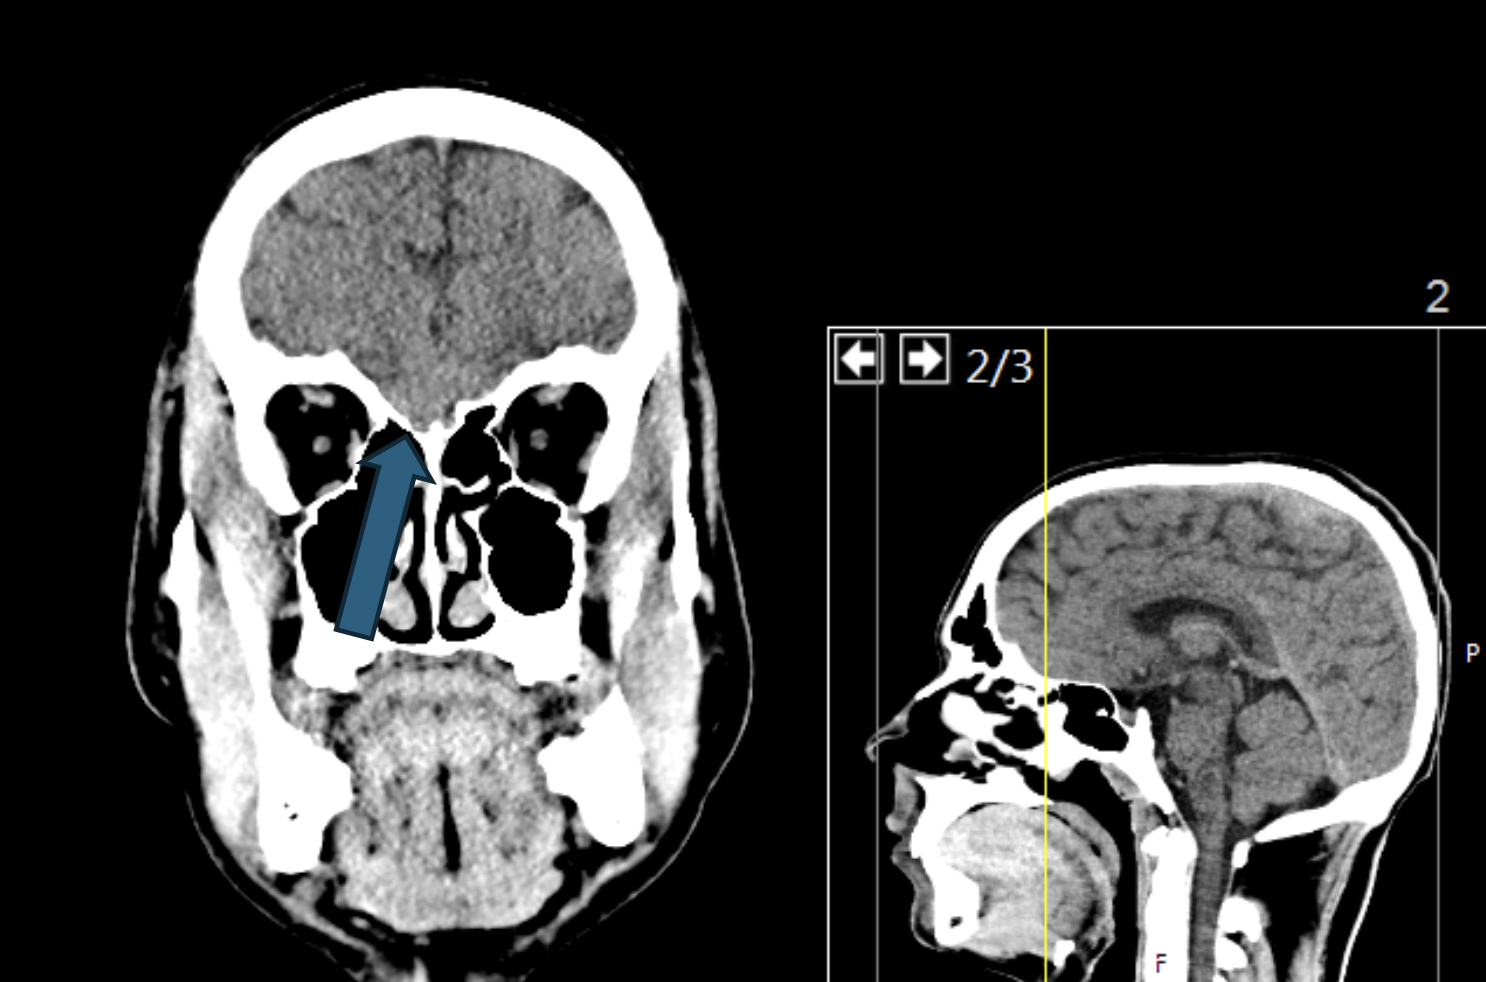

2.90 In der abgebildeten frontalen CT-Schicht des menschlichen Schädels markiert ein weißer Pfeil eine bestimmte anatomische Struktur. Welche der folgenden Hirnareale stellt das primäre Ziel der Projektionen der Neurone bzw. Axone dar, die in diesem markierten Bereich lokalisiert sind?

Antwortmöglichkeiten

- (A) N. opticus

- (B) Fila olfactoria

- (C) N. trigeminus

- (D) N. petrosus major

- (E) N. petrosus minor